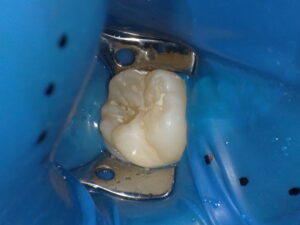

虫歯を取り除いた後、ラバーダムを装着し唾液が来るのを防ぎます。

歯科用の接着剤を塗布します。(ラバーダムをしているのでお子さんも安心です)

自費専用のコンポジットレジンを充填します。その際にもともとの歯の形、溝、色調を再現します。(ここが1番時間がかかるところですし、こだわりポイントです)